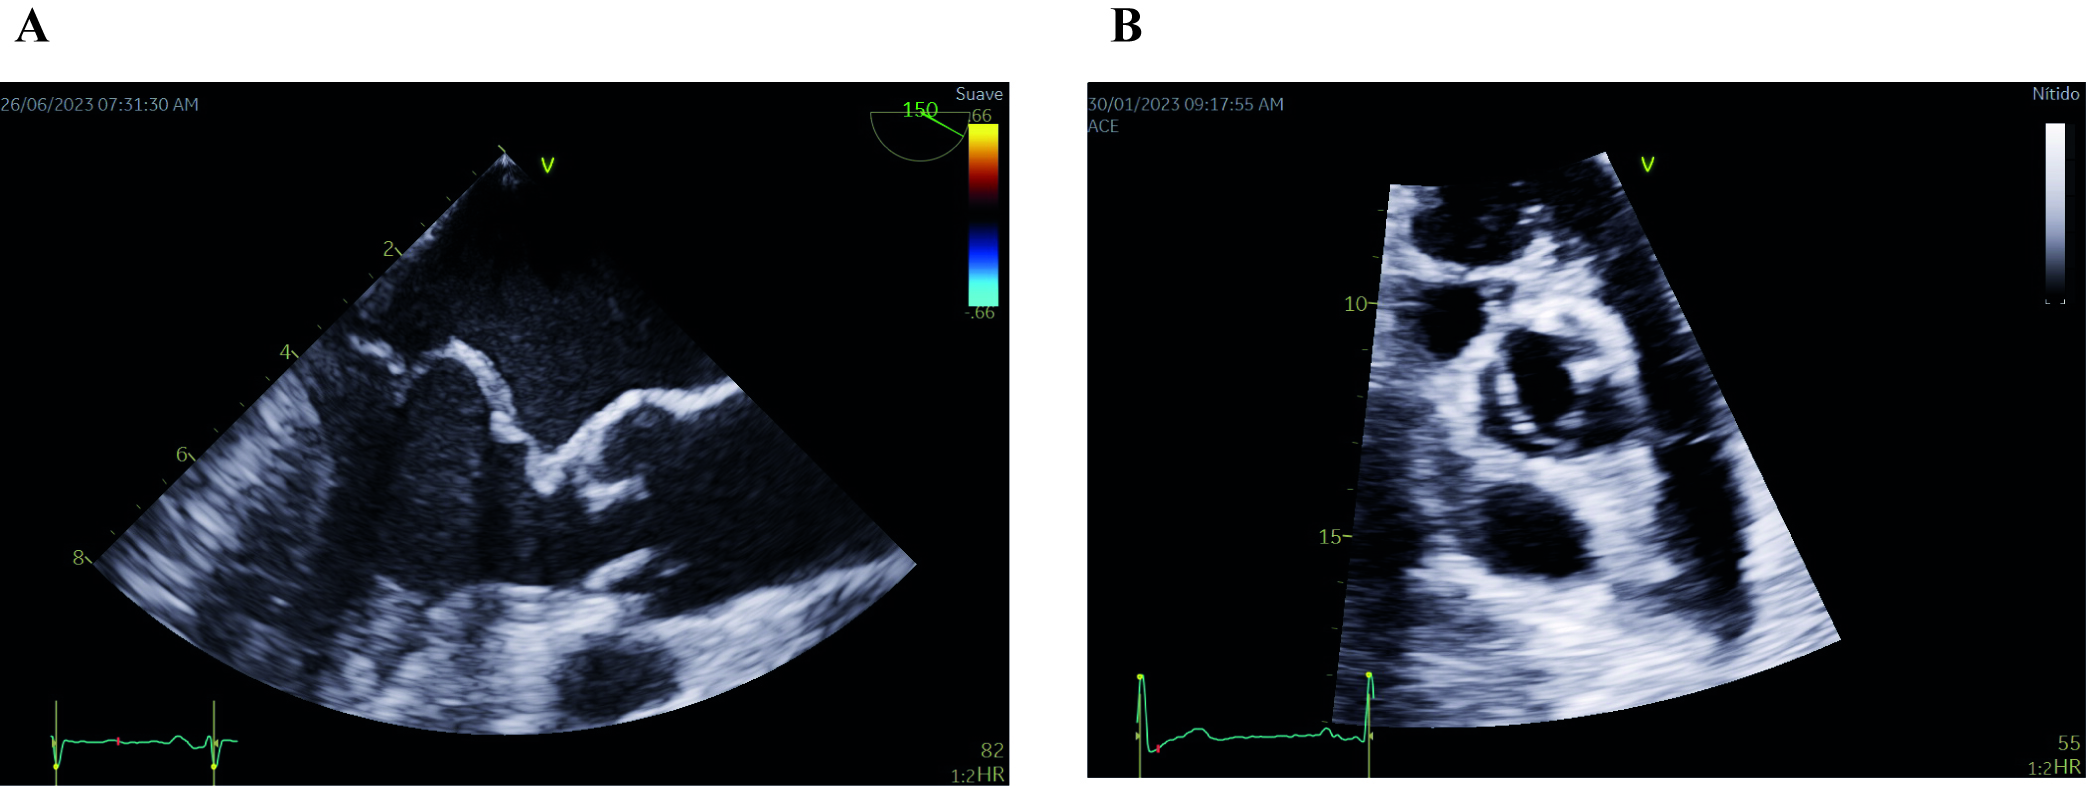

Fig. 2.

Fig. 2.Echocardiographic images of mitral valve prolapse of both leaflets (A) and bicuspid aortic valve (B). (A) Midesophageal long-axis transesophageal echocardiographic image depicting mitral valve prolapse of both leaflets. Note that both leaflets are beyond the valvular plane, protruding into the left atrium, when the mitral valve is closed (B) Parasternal short-axis transthoracic echocardiographic image showing a bicuspid aortic valve with fusion of both coronary leaflets. A raphe is present between the fused leaflets.

BAV is the prevailing valve abnormality found in around 0.5–2% of the general population [48]. It is characterized by an aortic valve that has only two cusps, or flaps, instead of the usual three (Fig. 2B). BAV follows an autosomal pattern of inheritance with incomplete penetrance, variable expressivity and male predominance in a 3:1 ratio [49]. More than 35% of individuals with BAV will experience various complications, including aortic valve stenosis and regurgitation, as well as ascending aortic aneurysms and dissection. Studies have shown a high incidence of thoracic aortic aneurysms (TAA) in BAV patients and their family members, suggesting that both TAA and BAV may share a common genetic cause [50, 51].